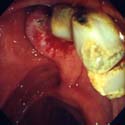

³»½Ã°æÀû

´ã¼® Á¦°Å¼ú

³»½Ã°æÀû ¿ªÇ༺ Ãé´ã°üÁ¶¿µ¼ú(ERCP)¸¦

½ÃÇàÇÏ¿© ´ã°ü ³»¿¡ ´ã¼®À» ¾Ë¾Æ³À´Ï´Ù(±×¸²

1). ´ã¼®À» Á¦°ÅÇϱâ À§ÇØ ¸ÕÀú ½ÊÀÌÁöÀå¿¡

À§Ä¡ÇÑ, ´ãµµ ÀÔ±¸ÀÎ À¯µÎºÎ¸¦ Àü±â Ä®·Î

Àý°³ÇÑ ÈÄ(±×¸² 2) ±Ý¼ÓÁ¦ ¹Ù½ºÄÏÀ̳ª

dz¼±À» ÀÌ¿ëÇÏ¿© ´ã°ü³» ´ã¼®À» Á¦°Å(±×¸²

3, 4)ÇÕ´Ï´Ù.